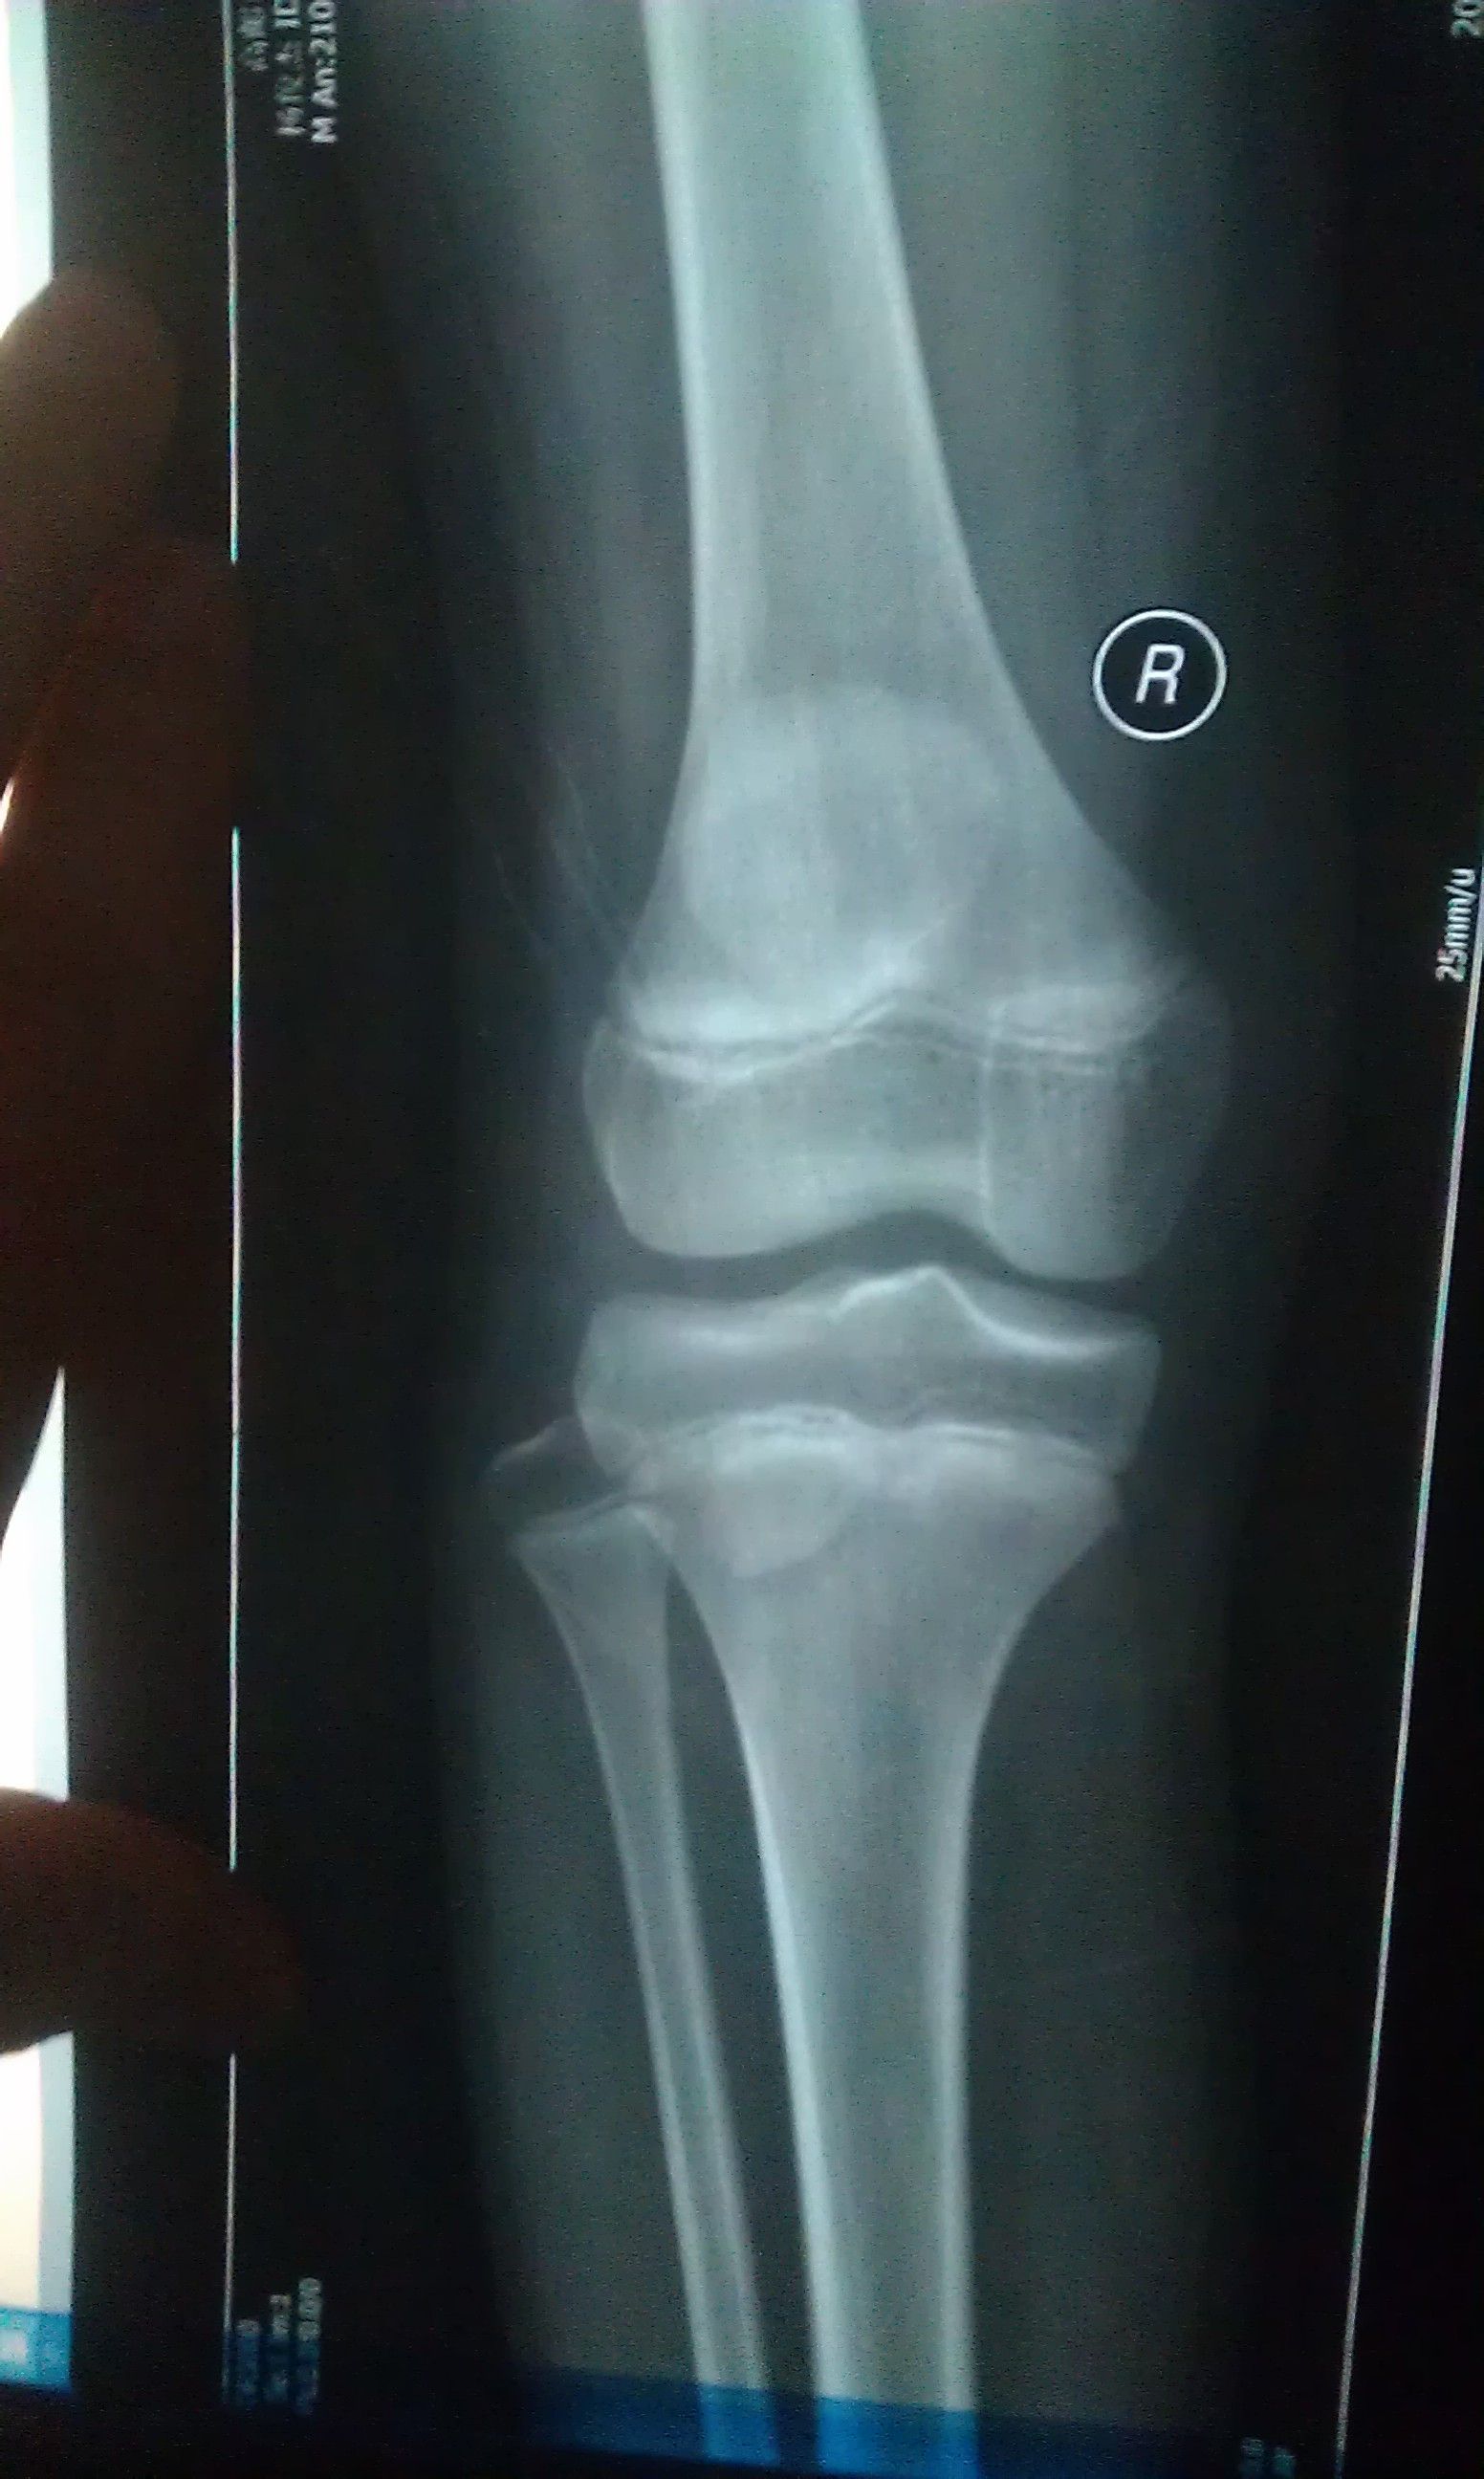

我小孩在近一个多月 下蹲 上站时 膝盖下面总是疼(按他说的意思我在图3标了一下),一开始是右腿,现

在是两条腿的相同部位都有这现象,一边疼的时候去医院看过,也拍了X片(见图1、2),医院医生没说什么,开了药和膏药,说吃完了还疼再去给他看,是不是风湿性关节炎(病历和药见图4)。我们家长不放心这医生,在这想请在线医生帮帮忙,分析一下我孩子的X片 !不胜感激!

病情分析: 你好,从你的叙述来看,考虑属于生长痛的可能性较大。这种情况的发生多因孩子活动量相对较大,长骨生长较快,与局部肌肉肌腱的生长发育不协调,导致了生理性疼痛的发生。不是风湿性关节炎 指导意见: 出现生长痛现象是一般不需要特殊治疗。疼痛发作时最有效的处理方法是为孩子作局部按摩、热敷,帮助减轻疼...痛程度,使小孩的心理得到关怀和安全感。 也可以使用食疗的方法,淮山药250克,猪蹄筋(其他动物蹄筋也可以)100克,调料适量,将蹄筋泡软、洗净、切段,加清水适量炖沸,调入山药及调料,文火炖熟服食。很快就能好转的。希望能对你有所帮助。